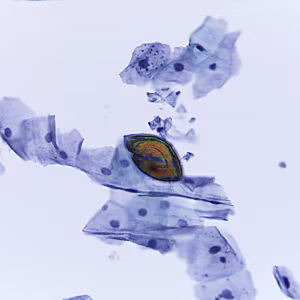

2018 DPDx Case Studies

DPDx is an educational resource designed for health professionals and laboratory scientists. For an overview including prevention, control, and treatment visit www.cdc.gov/parasites/.